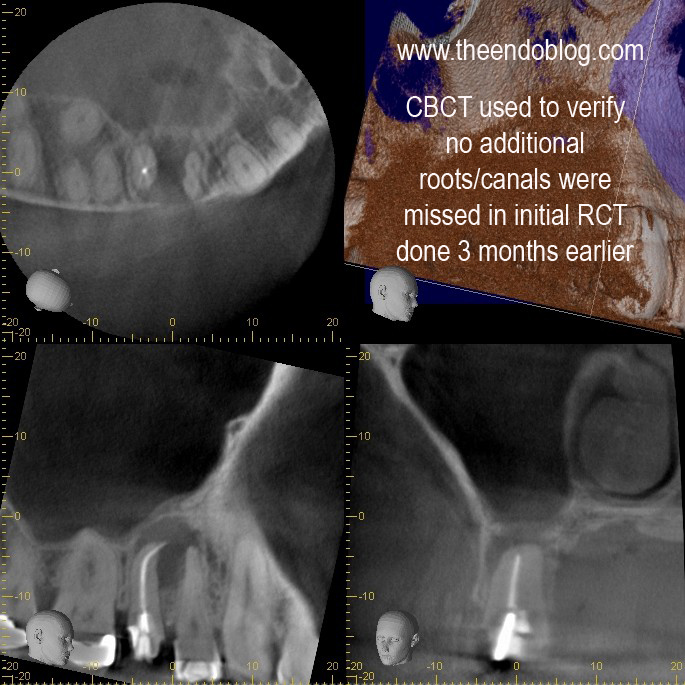

This root canal was done by her general dentist 3 months earlier.  As you can see it is overfilled, post placed, crown prepped and ready for new crown, but patient continues to have symptoms with the tooth.

CBCT taken to evaluate the root morphology. It is clear that this is a single root/canal.  (The canal has an oblong shape)  It was chosen to treat this tooth with apical surgery to preserve the restorative work that has been completed and assure that the overextened gutta percha is removed.

Apicoectomy completed with MTA retrofill.

9 month recall show complete healing of the periapical lesion, tooth is fully functional and asymptomatic.  This procedure saves the patient significant time and money over extraction and implant placement.